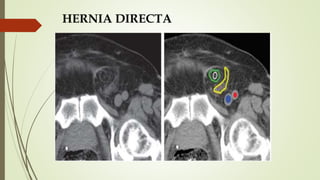

HERNIA DIRECTA

 Pasa anteromedial a vasos epigástricos inferiores

 Masa lateral a músculo recto

 «Signo lateral cresciente»

 CI desplazado y comprimido lateralmente, incluyendo grasa y demás

contenidos